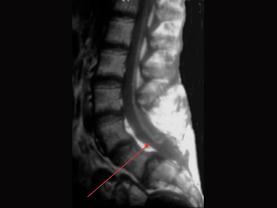

关于脊髓栓系综合征不正确的是 ( )A、下肢感觉障碍B、下肢肌肉一般为痉挛性瘫痪C、脊髓低位D、大小便失禁E、终丝变粗

问题 关于脊髓栓系综合征不正确的是 ( )

选项 A、下肢感觉障碍 B、下肢肌肉一般为痉挛性瘫痪 C、脊髓低位 D、大小便失禁 E、终丝变粗

答案 B